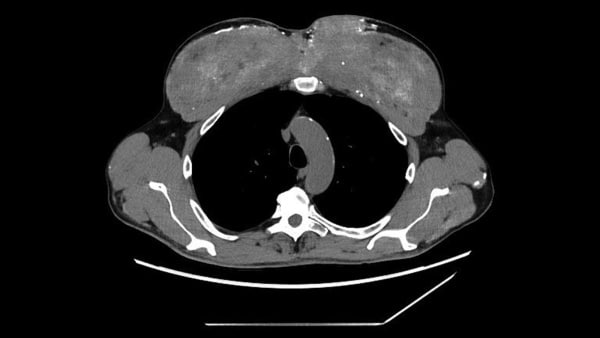

The departed: A 39-year-old male in the United States

The post-mortem examination findings: Medical professionals assessed the man following a fatal altercation, where a stab wound had perforated a vessel inside his lungs. They observed that the individual’s heart was somewhat enlarged and that he exhibited moderate atherosclerotic coronary artery disease (CAD) within a pair of vessels. CAD arises from the accumulation of plaque along the arterial walls leading to the heart.

They recognized this structure as the os cordis — a “cardiac bone” infrequently, if ever, spotted in humans.

What renders the case exceptional: The os cordis has historically been detected in nonhuman mammals, notably ruminants like cattle and camels. Within animals, it is thought to bolster the cardiac valves responsible for governing the circulation of blood inside the heart.

Although the authors of the case report remained ignorant of the man’s comprehensive medical background, they observed that the emergence of an os cordis could quite possibly be linked to his apparent cardiac ailment. It is recognized that aging and illness could also sway this formation within other animals, they incorporated.